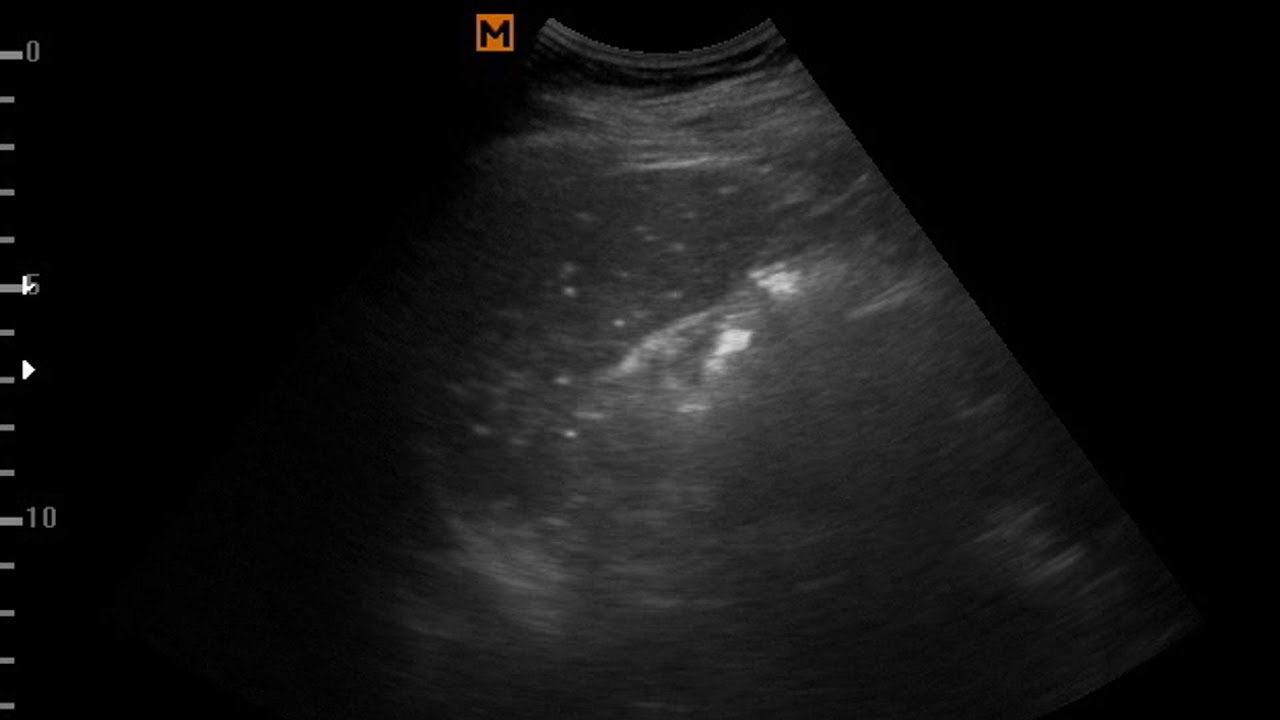

From radiologykey.com

Conventional ultrasound findings in chronic liver disease Radiology Key How To Cure Liver Granuloma Learn about the tests and procedures used to diagnose hepatic granulomas, a condition characterized by the presence of. In some cases, the cause may remain unknown. This article provides an overview of hepatic granulomas, including their causes, symptoms, and available treatment options. Early detection of hepatic granulomas is crucial to prevent complications. Hepatic granulomas are small abnormal clumps of cells. How To Cure Liver Granuloma.